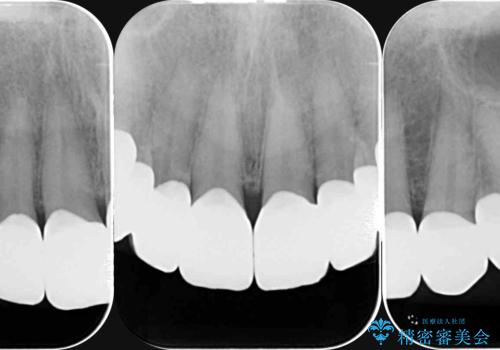

ラミネートを丁寧に除去したのち、ジルコニアクラウンを作製し審美性の回復・向上を計画します。

- 88万円(仮歯・ジルコニアクラウン×8)費用は治療当時の料金となります